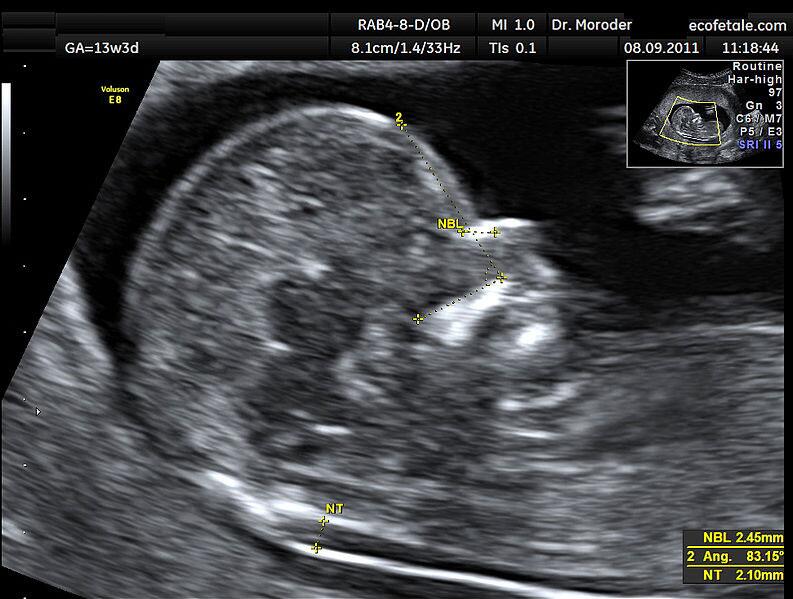

七、正矢位B超图参考

图片来自维基百科的NT超声图

NT检查的正常值在不同地区不同医院都的标准都会有所差异,奶爸目前所知的就有2.5mm、3.0mm、3.5mm这3个标准。总之,超过正常值,NT越厚,风险就越大。

1、做NT对医生的测量技术要求非常高,稍微有些偏差,就有可能会有零点几毫米的误差。NT增厚,先检查B超图片是不是正矢位,不是正矢位肯定会有误差,建议复查。